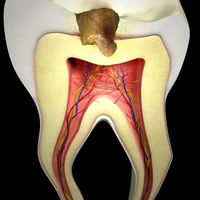

Carie profonde

Affections de la pulpe dentaire